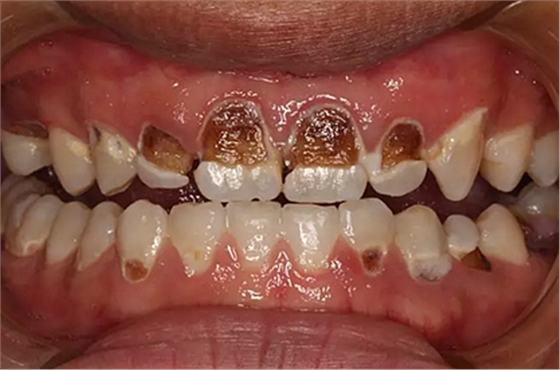

我們的主人今年才25歲,可卻從很小的時(shí)候就嗜好喝可樂等碳酸飲料,幾年下來,讓我們兄弟姐妹們整天浸在碳酸里受這蝕骨之痛,原本皎潔的外貌如今早己經(jīng)是腐蝕不堪、丑陋無(wú)比,更有甚者,一些兄弟姐妹們已經(jīng)病入膏肓,被病痛折磨奄奄一息。

下面是醫(yī)生眼中和ct下的我們

一身病痛啊

牙結(jié)石、牙齦炎癥、牙體殘缺、慢性牙髓炎、蛀牙......

才二八芳華的我們

已經(jīng)滿目蒼夷

再來看看曾經(jīng)的我們